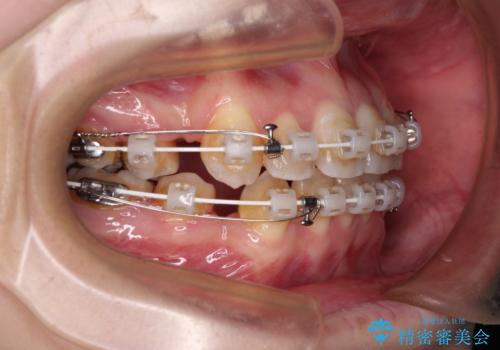

- 矯正装置

- 審美装置

デコボコが強いため小臼歯4本を抜歯し、上顎正中を左側に移動させるために補助装置を使用して、ワイヤー装置にて矯正治療を行うこととしました。